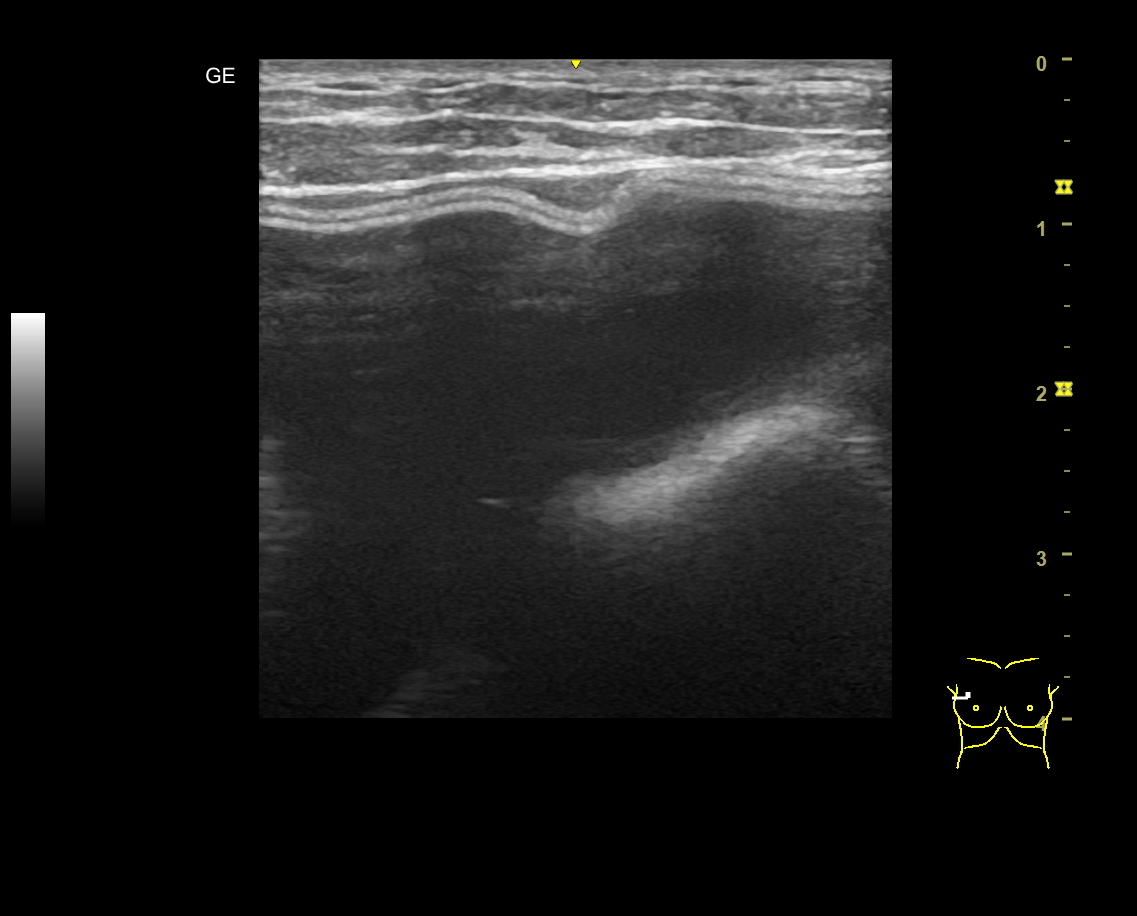

40代女性の豊胸バッグ入れ替え症例になります。十数年前に乳腺下に豊胸術をされましたが、被膜拘縮によってお胸の変形を生じてしまいました。 当院で乳がんエコー検診の際に、入れ替えをお勧めしたのがきっかけて手術を行っています。。

入れ替えにあたっては、バッグのサイズを以前のよりもサイズの大きな285ccに変更し、大胸筋と被膜の間にスペースを再作成しています。止血と剥離の容易さを考慮し、アンダー切開としました。

術後写真は3ヶ月後ですが、拘縮の再発なく、自然な形状と柔らかな感触をつくる事ができました。